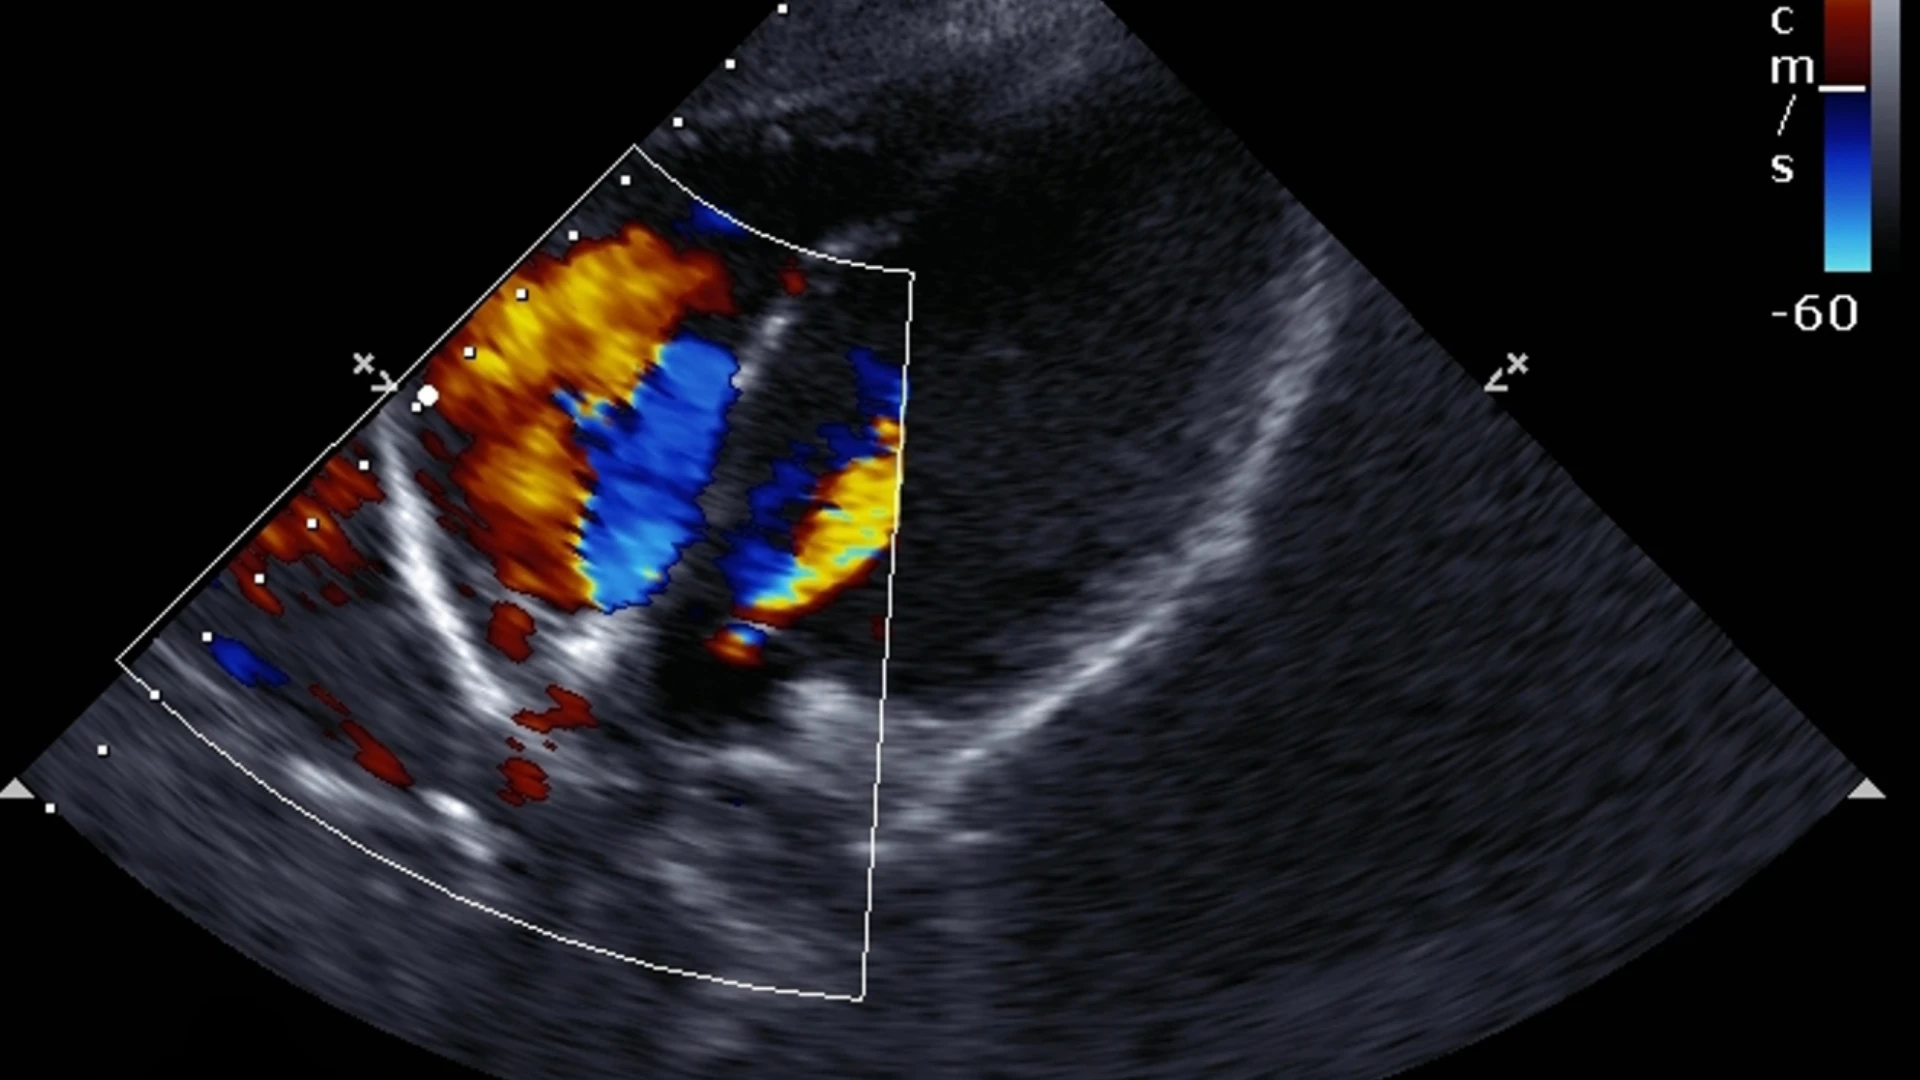

Процедура є безболісною, займає близько 20–30 хвилин і не потребує спеціальної підготовки. Лікар використовує ультразвуковий датчик, який передає зображення серця на монітор у режимі реального часу. Це дозволяє оцінити:

- Структуру та функцію клапанів;

- Скорочувальну здатність міокарда;

- Рівень кровотоку в камерах серця.